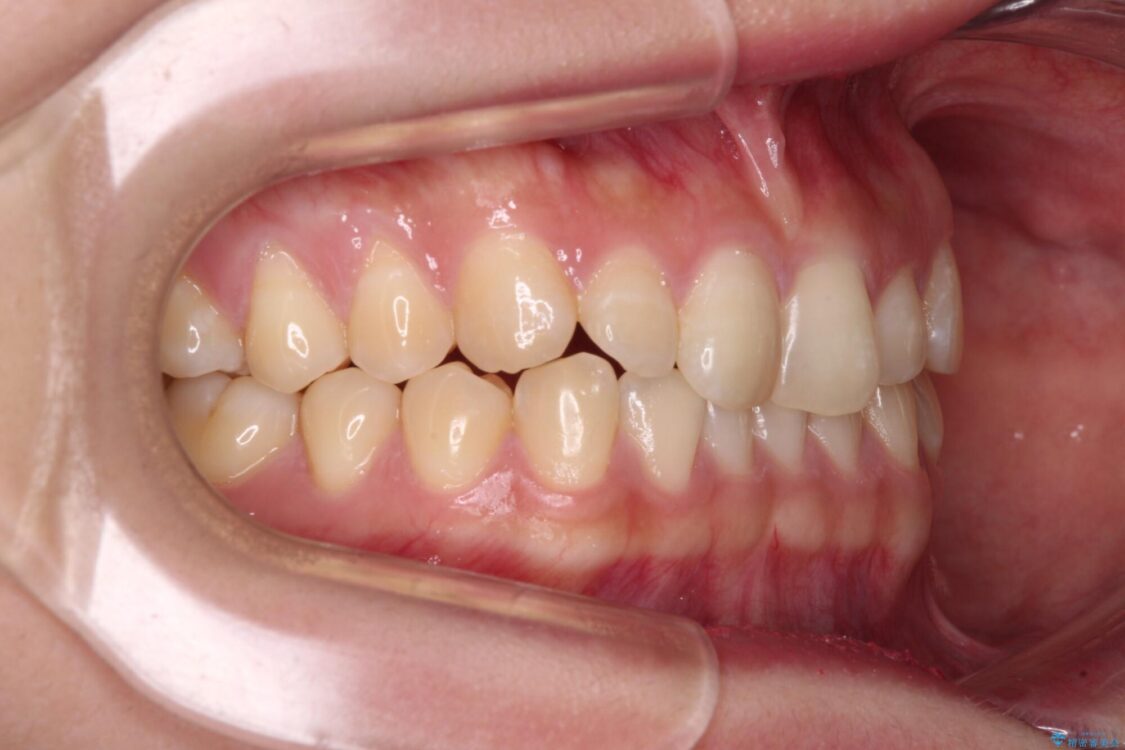

根管治療を行ったままの奥歯と、矯正治療の後戻りを気にして来院された患者様です。

矯正治療の後戻りは軽微であったため、インビザラインの簡易パッケージであるインビザライン・ライトを用いて歯列を整えることとしました。

クラウンはよりよい咬み合わせで装着したいため、インビザラインを1セット使用して概ね歯列を整えた時点で補綴治療を行い、その後仕上げの矯正治療を行いました。

治療前

• 治療途中の奥歯と矯正治療の後戻り インビザライン・ライトによる矯正治療 治療前画像